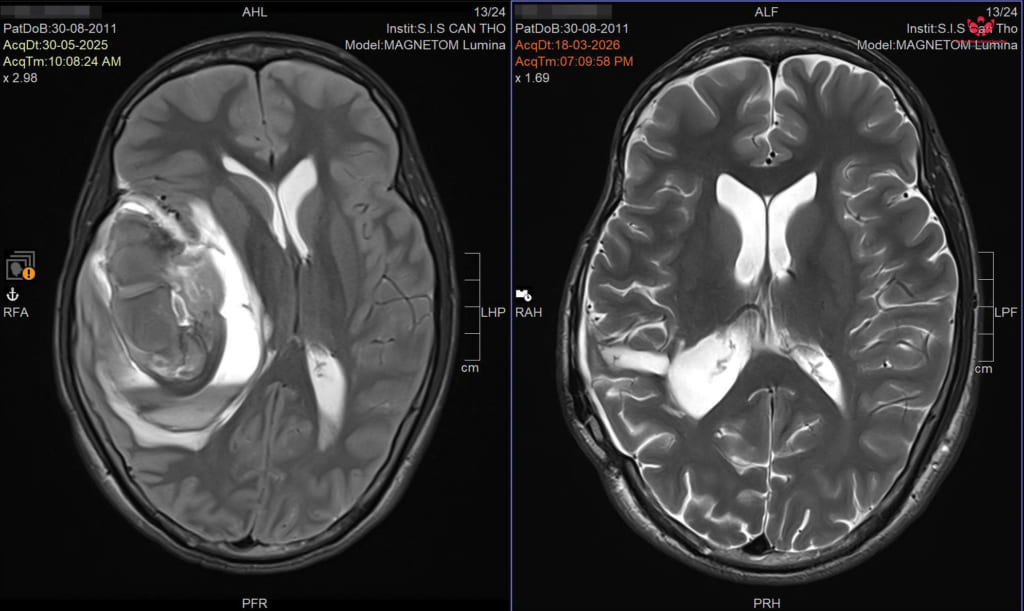

Hình ảnh chụp cộng hưởng từ MRI não của nam sinh Trước và Sau điều trị.

Tại Bệnh viện Đa khoa Quốc tế S.I.S Cần Thơ, các bác sĩ nhanh chóng xác định em bị xuất huyết não do vỡ dị dạng mạch máu não (AVM). Đây là bệnh lý dị dạng mạch máu bẩm sinh, thường không có biểu hiện đặc biệt, cho đến khi chúng dọa vỡ hoặc đã vỡ với những cơn đau đầu đột ngột dữ dội và có thể cướp đi tính mạng trong thời gian rất ngắn.

BS.CKI Nguyễn Quang Hưng – Trưởng Đơn vị Phẫu thuật Thần kinh, cho biết, trong trường hợp này, bệnh nhân có dị dạng mạch máu não khá phức tạp đã vỡ kèm theo khối máu tụ lớn, do đó các bác sĩ đã lựa chọn chiến lược điều trị phối hợp nhằm tối ưu hiệu quả.

“Ngay khi nhập viện, bệnh nhân được cấp cứu và đánh giá nhanh, sau đó tiến hành can thiệp nội mạch để giảm lưu lượng dòng chảy, hạn chế nguy cơ chảy máu. Tiếp theo, ê-kíp phẫu thuật thần kinh thực hiện bóc tách và loại bỏ toàn bộ khối dị dạng.” – BS.CKI Nguyễn Quang Hưng thông tin.